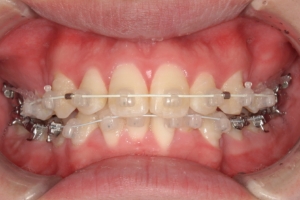

BEFORE

治療前

PROCESS

半年

AFTER

治療後

上下顎の叢生量(ガタガタの量)が中等度で、上顎前歯が唇側に傾いてとび出ていたので、そうした問題を改善するために小臼歯の抜歯が必要と診断しました。初診時の口元のライン(Eーライン)がきれいでしたので、治療過程で口元が引っ込みすぎないように注意しました。治療後は噛み合わせが良くなり、口元のラインも概ね維持ができたため、患者さまにも非常に満足していただけました。